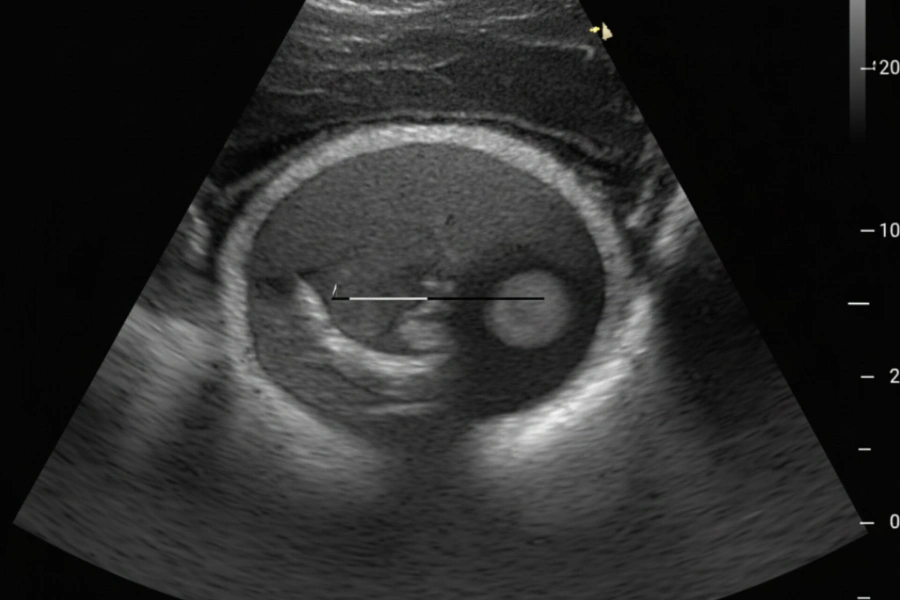

نقش سونوگرافی در تشخیص فیبرآدنوم پستان

سونوگرافی پستان یکی از مهمترین و پرکاربردترین روشها برای تشخیص فیبرآدنوم بهویژه در زنان جوان است. از آنجا که بافت پستان در سنین پایین متراکمتر است، ماموگرافی ممکن است دقت کمتری داشته باشد، در حالی که سونوگرافی قادر است تودهها را با وضوح بالاتری نشان دهد.

ویژگیهای فیبرآدنوم در سونوگرافی

در سونوگرافی، فیبرآدنوم معمولاً دارای ویژگیهای زیر است:

- توده هیپواکو (تیرهتر از بافت اطراف)

- شکل بیضی یا گرد

- حاشیههای صاف و منظم

- جهت موازی با پوست (wider than tall)

- عدم تهاجم به بافتهای اطراف

این ویژگیها به رادیولوژیست کمک میکند تا توده خوشخیم را از ضایعات مشکوک افتراق دهد.

نقش سونوگرافی در پیگیری

سونوگرافی نهتنها برای تشخیص اولیه، بلکه برای پیگیری تغییر اندازه توده، ارزیابی رشد سریع و بررسی چندکانونی بودن ضایعات بسیار مفید است و معمولاً هر ۶ تا ۱۲ ماه انجام میشود.

سونوگرافی چه نقشی در تشخیص فیبرآدنوم دارد؟

سونوگرافی اصلیترین روش تشخیص فیبرآدنوم، بهویژه در زنان جوان است. این روش میتواند شکل، اندازه و ویژگیهای توده را مشخص کرده و به افتراق ضایعات خوشخیم از بدخیم کمک کند.

آیا سونوگرافی بهتنهایی برای تشخیص کافی است؟

در بسیاری از موارد بله. اما اگر ویژگیهای توده غیرمعمول باشد یا رشد سریع داشته باشد، ممکن است پزشک انجام بیوپسی را برای اطمینان بیشتر توصیه کند.

تفاوت فیبرآدنوم با کیست پستان چیست؟

فیبرآدنوم یک توده جامد است، در حالی که کیست پستان پر از مایع میباشد. سونوگرافی بهخوبی میتواند این دو را از یکدیگر تفکیک کند.